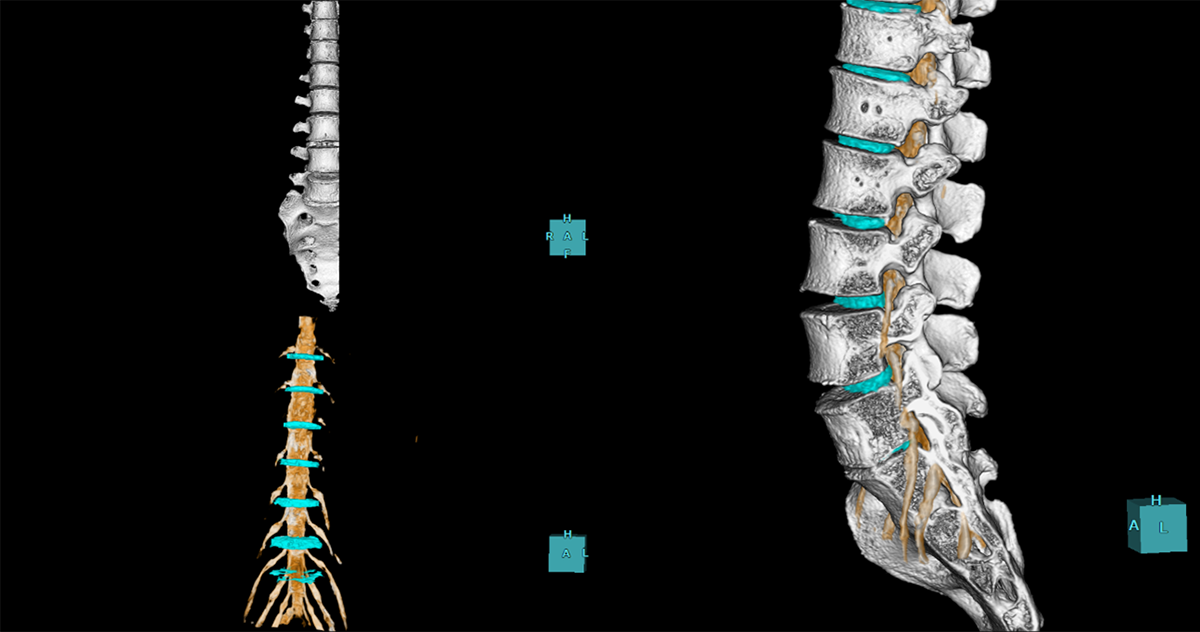

腰神経セグメンテーションは、MRI画像から自動で腰神経の抽出を行います。CTの骨画像とMRIの腰神経抽出画像を重ね合わせて観察が可能です(図3)。

図3 腰神経セグメンテーションとCT骨画像との重ね合わせ